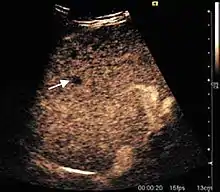

The ultrasound appearance is a well defined lesion, with very thin, almost unapparent walls, without circulatory signal at Doppler or CEUS investigation. The content is transonic suggesting fluid composition. The presence of membranes, abundant sediment or cysts inside is suggestive for parasitic, hydatid nature. Posterior from the lesion the acoustic enhancement phenomenon is seen, which strengthens the suspicion of fluid mass. They typically displace normal liver vessels but no vascular or biliary invasion occurs.

Hydatid liver cyst. Diagnostic criteria are the presence of membranes and sediment inside.